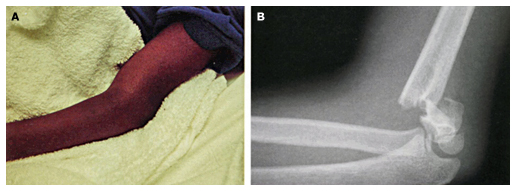

Supracondylær humerus fraktur hos børn.

Gartland type I Udisloceret men ansamling. Gips i 3 uger

Gartland type II Bagud disloceret med bevaret bagerste cortex

Gartland type III Total dislocation

Gartland type III